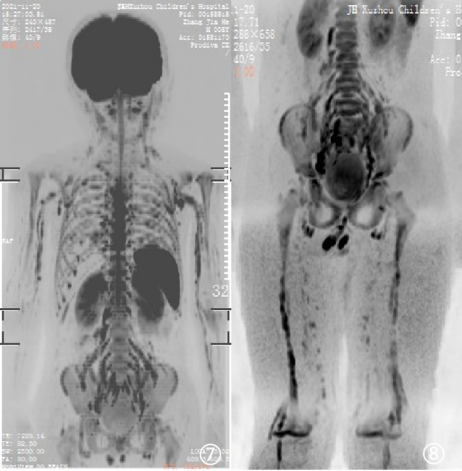

图①~⑧ 男,8岁,神经纤维瘤病1型,有家族史,全身多发结节及包块。图①~③ T2WI压脂成像;图④~⑥ MRI类PET成像;图⑦⑧ MRI类PET 3D后处理成像。

WB-DWI技术采用全身大范围扫描,在抑制肌肉、脂肪、肝脏等组织背景信号的基础上,突出了病变的显示。原始图像采集完成后进行后处理,即可得到与PET图像极其相似的“类PET”图像。

WB-DWI常见临床应用如下:①肿瘤筛查:全身弥散成像可以一次性进行大范围扫描,敏感性高,能有效地寻找原发灶及全身转移病灶;②肿块的良恶性鉴别:“类PET”技术,可对病变作出初步的良恶性诊断,有利于临床治疗方法选择;③肿瘤化疗疗效及术后评估:“类PET”技术可对诸多肿瘤尤其是全身受累疾病的病灶作出准确、直观的显示。

总之,MRI类PET成像技术具有高组织分辨率及高时间分辨率特征,明显提高了病灶检出率,尤其对恶性肿瘤病灶检出、TNM分期、术前术后及疗效评估具有极高临床应用价值。